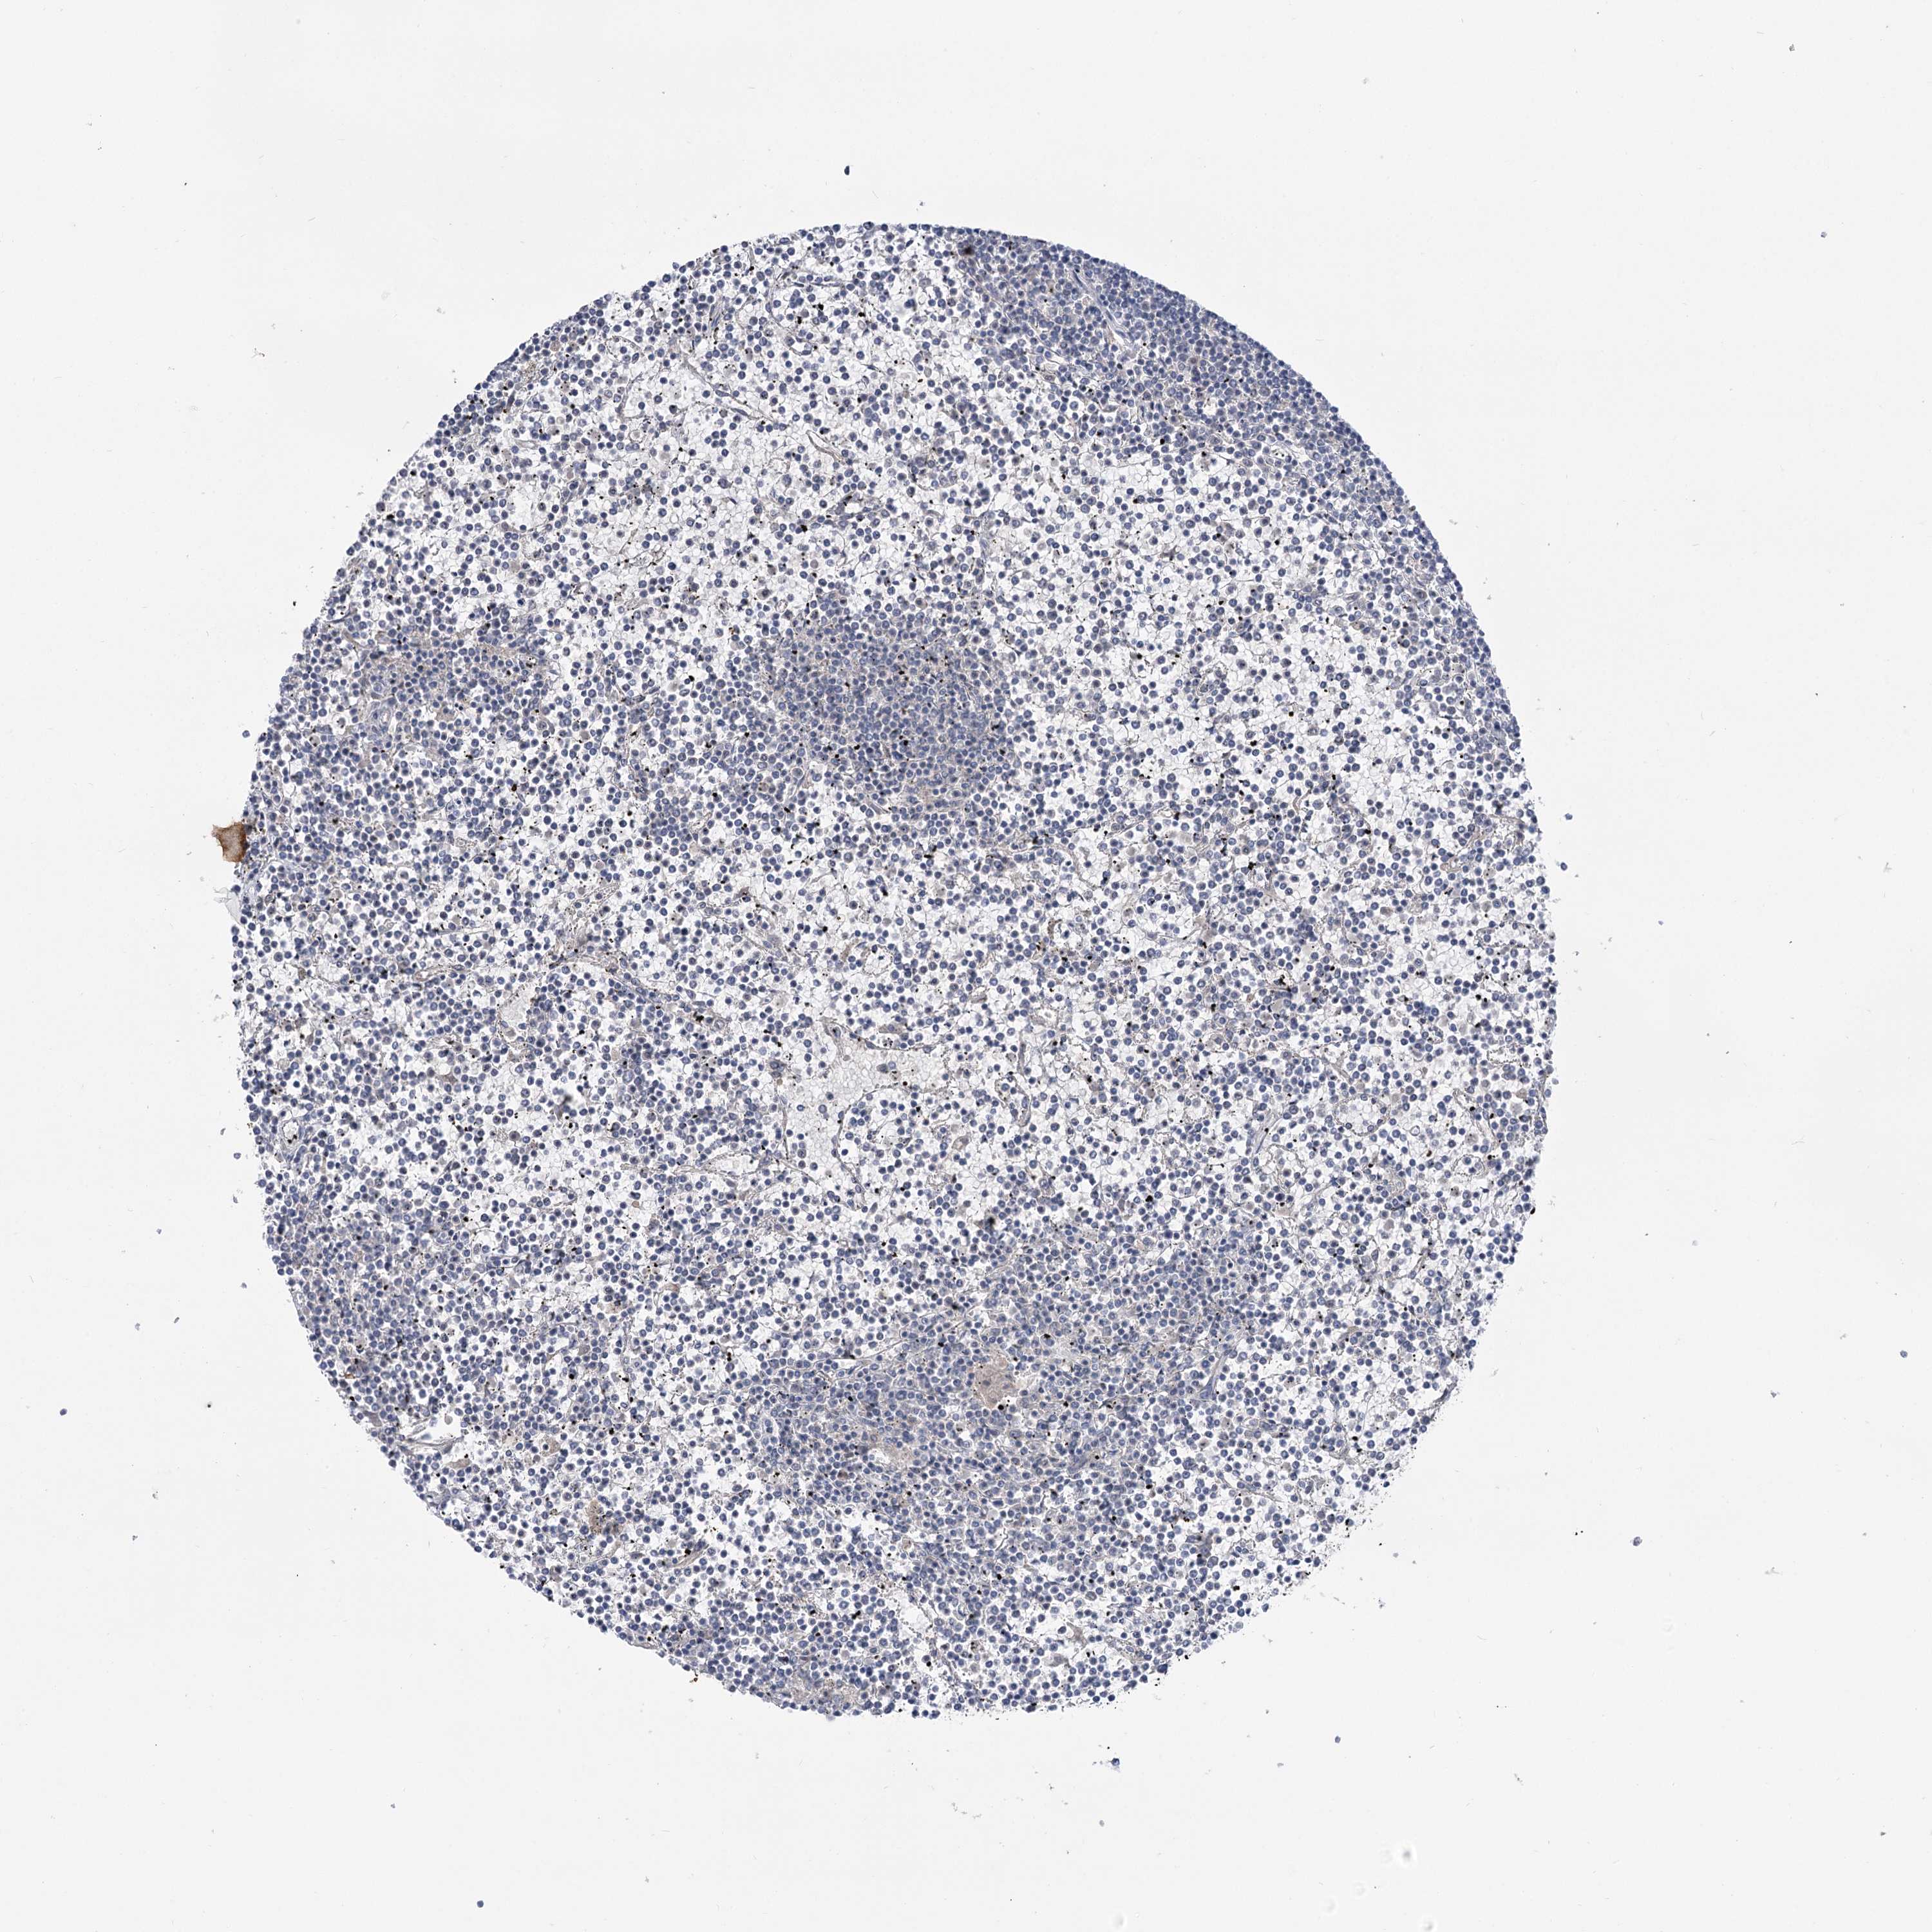

CANCER LYMPHOMA Show tissue menu

LYMPHOMA - Protein expressioni

A mouse-over function shows sample information and annotation data. Click on an image to view it in a full screen mode. Samples can be filtered based on level of antibody staining by selecting one or several of the following categories: high, medium, low and not detected. The assay and annotation is described here.

Antibody stainingi

Antibody staining in the annotated cell types in the current human tissue is reported as not detected, low, medium, or high, based on conventional immunohistochemistry profiling in selected tissues. This score is based on the combination of the staining intensity and fraction of stained cells.

Each image is clickable and will lead to virtual microscopy that enables deeper exploration of all samples and also displays staining intensity scores, fraction scores and subcellular localization as well as patient and tissue information for each sample.

Antibody HPA037759

Antibody HPA037760

Staining

High

Medium

Low

Not detected

Intensity

Strong

Moderate

Weak

Negative

Quantity

>75%

75%-25%

<25%

None

Location

Nuclear

Cytoplasmic/membranous

Cytoplasmic/membranous,nuclear

Hodgkin's disease, NOS

Malignant lymphoma, non-Hodgkin's type, High grade

Malignant lymphoma, non-Hodgkin's type, Low grade